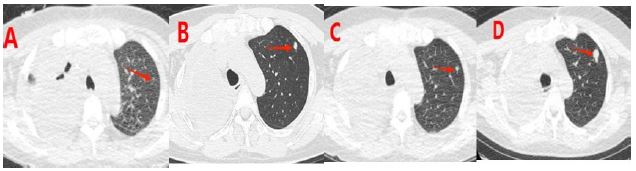

Over two months ago, the patient started coughing without an obvious cause, along with producing a small amount of white mucoid sputum and experiencing right-sided chest pain. A chest CT scan at a local hospital showed a 3.2 cm patchy shadow in the middle lobe of the right lung, along with pleural effusion. A percutaneous lung biopsy indicated a potential diagnosis of tuberculosis. She was diagnosed with secondary pulmonary tuberculosis and treated with the HRZE regimen for four weeks; however, her symptoms did not improve, and she developed new-onset dyspnea. A pulmonary artery CTA revealed a filling defect in the trunk of the right pulmonary artery, indicating a potential pulmonary embolism (Figure 1A & 1B).

The patient received interventional surgery on the pulmonary artery, followed by an endovascular biopsy guided by DSA, which collected fleshy tissue (Figure 1C, 1D, & 1E). The pathology report showed the following immunohistochemical results: Vimentin positive, focal smooth muscle actin positive, partial Desmin positive, and negative for S100, SOX-10, SS18-SSX, Myogenin, cytokeratin, CD34, STAT6, and EMA. Ki67 was greater than 80%. The pathological diagnosis was a spindle cell tumor of the pulmonary artery with necrosis, along with immunohistochemistry confirming intimal sarcoma (Figure 1F).

Figure 1: Imaging Diagnosis Process and Key Evidence for Pathological Diagnosis. (A) The maximum cross-sectional size of the shadow in the middle lobe of the right lung is approximately 85×73 mm, and a filling defect is visible in the main trunk of the right pulmonary artery (indicated by the arrow). (A & B) A filling defect is visible in the left pulmonary artery trunk (indicated by the arrow). (C & D) Pulmonary artery intervention surgery. (E) During the operation, tissue resembling fish meat and blood clots were extracted. (F) A spindle shaped multicell tumor with necrosis in the pulmonary artery, combined with immunohistochemistry, suggests arterial intimal sarcoma.